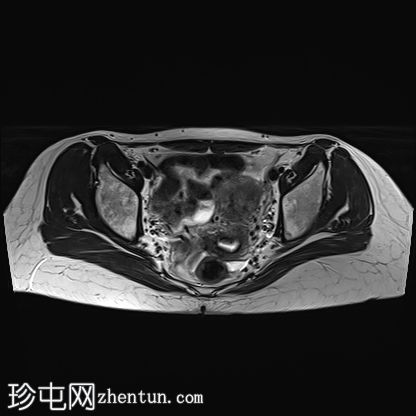

轴位

T2加权像